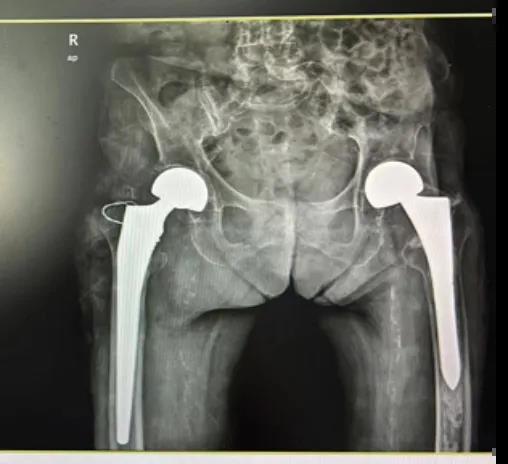

百岁人生,再启新程:近百岁老人成功完成第二次髋关节置换术

一位近百岁老人,成功挑战自我,完成了人生中第二次髋关节置换术,从卧床不起到行走自由,再次证明了年龄不是健康的枷锁。

钦州市浦北县有这样一位老人,岁月在她的脸上刻下了深深的痕迹,却未能磨灭她眼中的光芒。罗奶奶,今年97岁高龄,是邻里间公认的“不老松”。然而,岁月不饶人,4年前的一次意外导致罗奶奶左股骨粗隆间骨折,在当地医院经过一次成功的髋关节置换手术后,重新站了起来。但是在今年8月初她不慎跌倒致右股骨粗隆间骨折,家属再次送到当地医院欲行手术治疗,当地医院行冠脉造影提示冠心病(三支病变,部分节段严重狭窄),认为其体质较虚弱合并严重的内科疾病,手术风险较高,不敢为其手术。随后家属带着罗奶奶住院资料到我院门诊咨询,外科与内科医生了解病情后告知家属有信心调理稳定罗奶奶的内科疾病,创造手术机会。听到医生的建议,家属急忙把罗奶奶转到我院,等待下一步的检查和治疗。

手术室内,我院髋关节二科团队凭借精湛的技术和丰富的经验,小心翼翼地进行着每一步操作。经过1小时的努力,手术终于圆满成功。当罗奶奶被推出手术室,那一刻,亲人攥紧的心都松了下来,掌声与泪水交织在一起,为罗奶奶的勇气和医生的精湛技术喝彩。

“医术精湛,情暖人心;医德高尚,百问不厌 。”出院当天,家属赠送了锦旗和发自肺腑写的感谢信,深切地表达了对医护人员的感激和敬意。罗奶奶经历两次髋关节置换手术重新站了起来,这不仅是她个人的胜利,更是医学与人性光辉共同闪耀的见证。愿这样的故事能够激励更多人对生命充满敬畏,保重身体,我们医护人员也会不忘初心,继续砥砺前行,为更多的患者带来健康与希望。